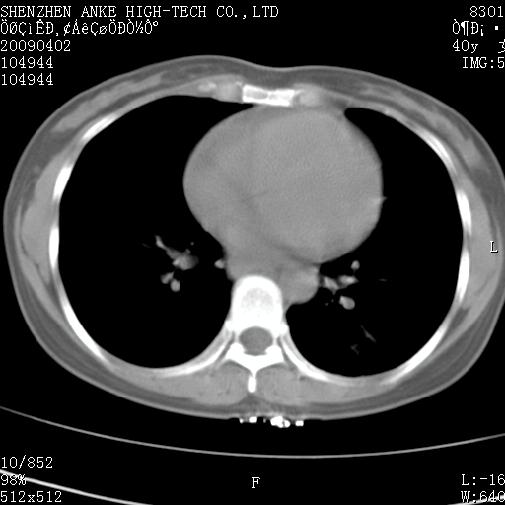

以下是引用随光逐影在2009-4-2 12:16:00的发言:[br]考虑左肺下叶背段继发性肺结核,结核球形成;建议追踪复查。

以下是引用gudu医生在2009-4-2 11:27:00的发言:[br]周围型肺癌

以下是引用卜一在2009-4-2 13:31:00的发言:[br][br] [br] 空洞壁厚不均 胸膜凹陷征。周围型肺癌可能 不排除干酪坏死型肺结核及坏死性肉芽肿。 [br] [br]支持!

以下是引用ct诊断高手在2009-4-2 13:04:00的发言:[br]空洞壁厚不均 胸膜凹陷征。周围型肺癌可能 不排除干酪坏死型肺结核及坏死性肉芽肿。